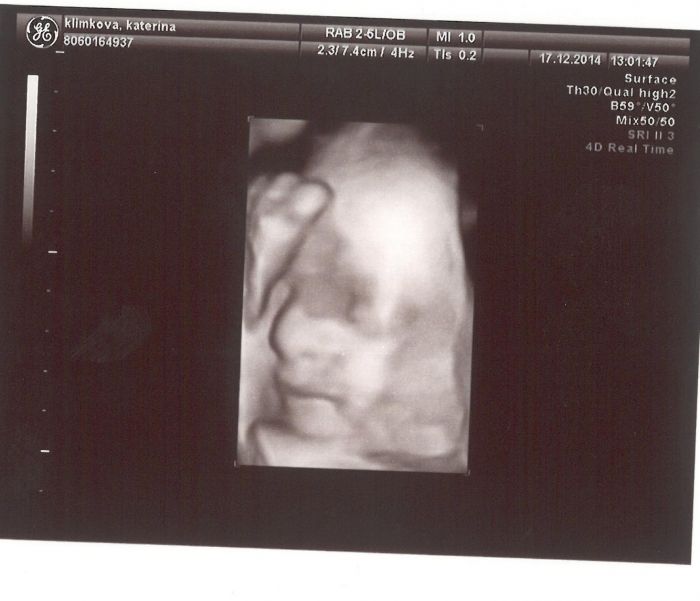

Díky holky, jste hodné. Já jsem na to také koukala, že to je normální váha, tak nevím co doktorka blbla :) Jinak s tím pediatrem jsem s ejí ptala, jestli ho už mám shánět a ona že už jsem ho dávno měla mít nakontaktovaného. Tak v lednu zkusím někoho najít... Jinak vám sem hodím fotky z 3D ultrazvuku. Mála Amélka se i smála a prý má nos po tátovi...to říkala ta doktorka. Ale přítel ho má nadvakrát zlomený, tak jsem zvědavá, co se nám narodí :)))) Ale zatím vypadá celkem lidsky :))))